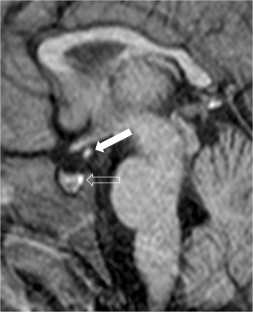

We selected pediatric head MRI examinations from 2005 to 2017 based on the finding of a double midline sellar and suprasellar bright spot on T1-weighted sequence. Medical history, physical examination, pituitary hormonal profile and bone age evaluation were extracted from the medical record of the selected patients. An experienced pediatric neuroradiologist reviewed head MRIs, which were performed on 3-tesla (T) magnet and included at least sagittal T1-weighted imaging centered on the sella turcica obtained with and without fat suppression.

In six cases, two midline bright spots were identified on T1-weighted sequences obtained both with and without fat suppression. While one spot was located at the expected site of the neurohypophysis in the posterior sella, the second one was in the region of the median eminence, suggesting partial ectopic posterior pituitary gland. Growth hormone deficiency, either isolated (n=1) or combined with thyroid stimulating hormone deficiency (n=1) was found. None of the children had clinical signs of posterior pituitary dysfunction.